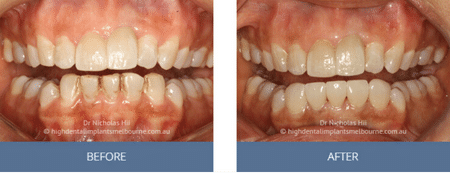

Clinical Before and After Photos

At High Dental, we believe a great smile changes everything. Our Smile Gallery showcases before-and-after images of patients who trusted us with their smiles. From veneers and crowns to full-arch implants, each result is unique — and each started with a consultation. Scroll through and imagine the possibilities for your own smile.

Before & After Disclaimer:

Images are provided for illustrative purposes only. Results shown relate to specific patients and individual outcomes may vary. A consultation is required to determine suitability for treatment.